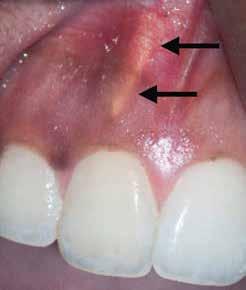

1. a–f ábrák: A cingulumon keresztül gömbfúróval kialakított hozzáférés a trepanációs kavitás labiális irányba történő túlzott mértékű kiterjesztését eredményezheti, és ez lényegesen növelheti a perforáció esélyét (a). A guttapercha átsejlik a lágyrészek alatt (b). Klinikailag igazolt perforáció (c). A preoperatív sagittális irányú CBCT-szeleten jól látható a labiális perforáció (d). Labiális irányú perforáció (fekete nyíl; e). A tényleges gyökércsatorna (piros nyíl; f).

2. a-b ábrák: A cingulumon keresztül gömbfúróval végzett trepanálás túlzott pericervikális dentin áldozattal, fordított tölcsér effektussal és perforációk kialakulásával járhat (fehér nyíl).